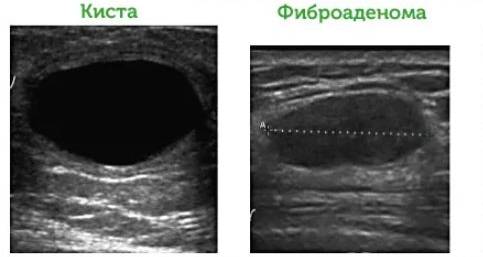

Отличия кисты и фиброаденомы

Киста, в отличие от фиброаденомы, обладает округлыми гладкими краями. Размеры этого образования могут варьироваться от 3 до 10 см. Структура кисты эластичная и более мягкая, она обычно располагается в верхнем квадранте молочной железы.

Чаще всего кисты возникают у женщин в возрасте 40-50 лет, тогда как фиброаденома может быть обнаружена и у молодых девушек. Поражение обеих молочных желез при кистах наблюдается довольно редко. В некоторых случаях особенно крупная киста может привести к деформации груди.

Фиброаденома, в свою очередь, отличается разнообразием размеров долей молочной железы и волокнистой структурой. При наличии этой опухоли может наблюдаться сужение молочных протоков. В некоторых случаях соединительная ткань молочной железы может разрастаться по кругу, а в других – прорастать в протоки.